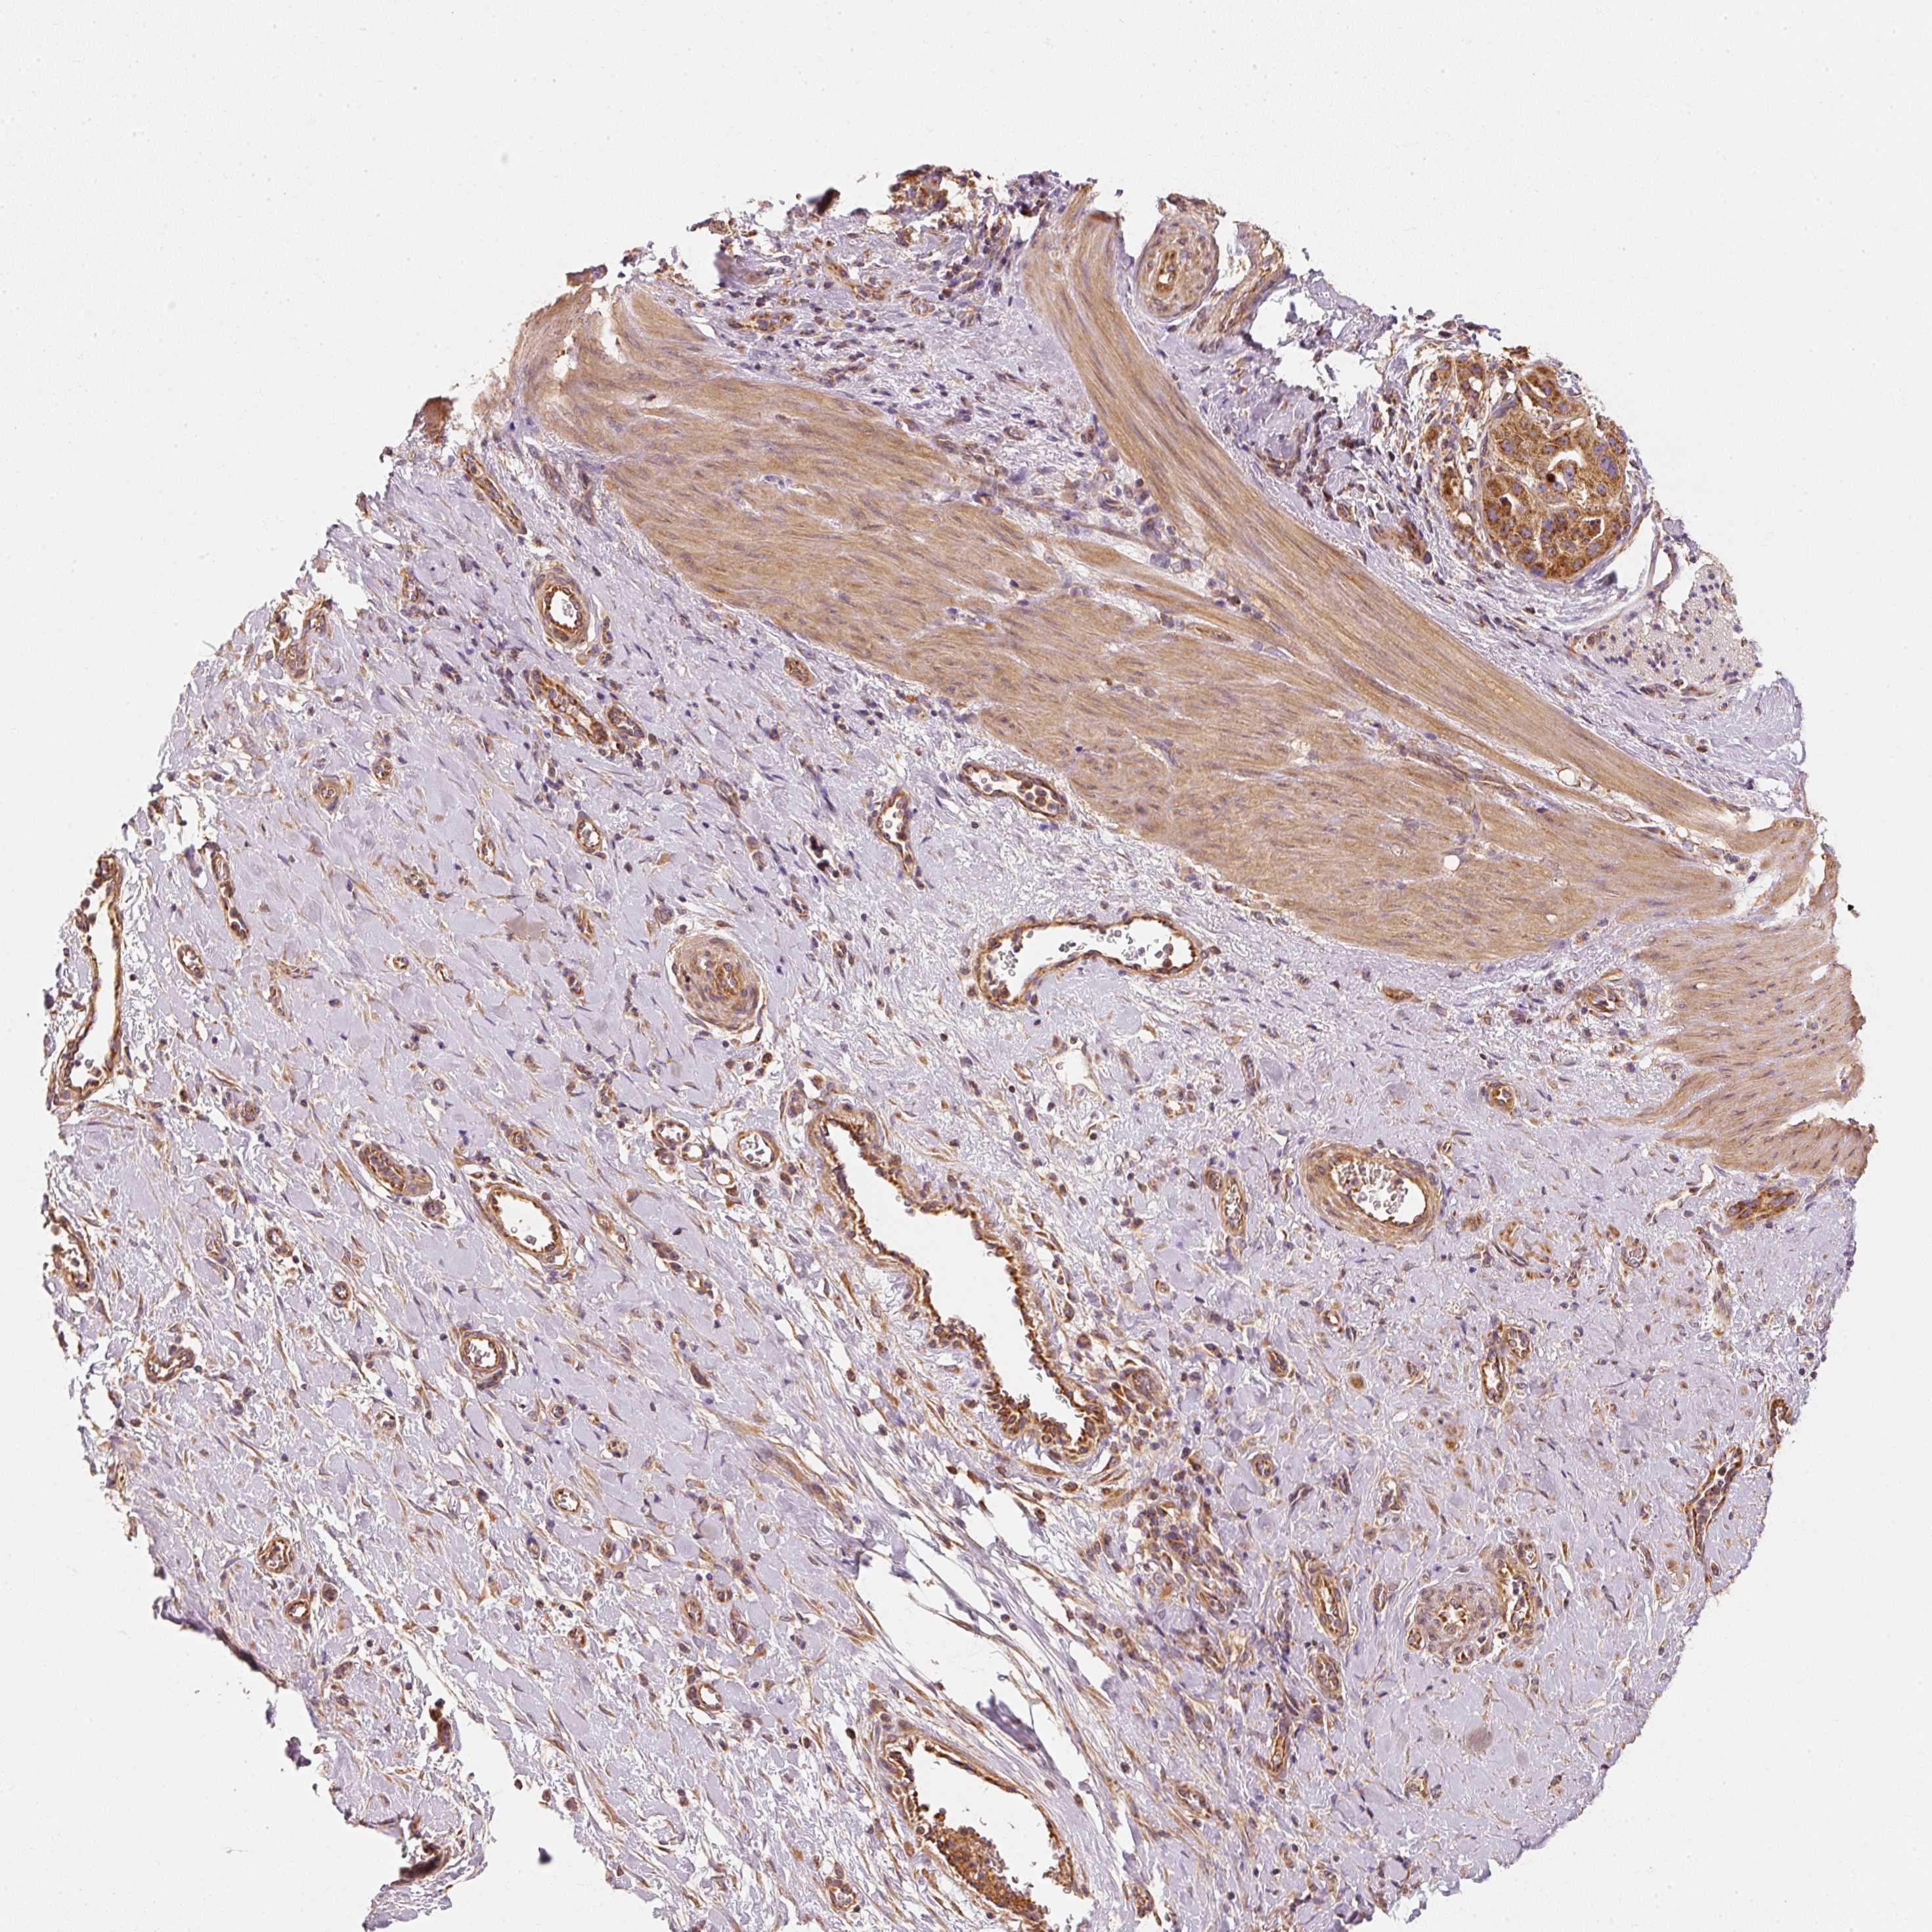

STOMACH CANCER - Protein expressioni

A mouse-over function shows sample information and annotation data. Click on an image to view it in a full screen mode. Samples can be filtered based on level of antibody staining by selecting one or several of the following categories: high, medium, low and not detected. The assay and annotation is described here.

Note that samples used for immunohistochemistry by the Human Protein Atlas do not correspond to samples in the TCGA dataset.

Antibody stainingi

Antibody staining in the annotated cell types in the current human tissue is reported as not detected, low, medium, or high, based on conventional immunohistochemistry profiling in selected tissues. This score is based on the combination of the staining intensity and fraction of stained cells.

Each image is clickable and will lead to virtual microscopy that enables deeper exploration of all samples and also displays staining intensity scores, fraction scores and subcellular localization as well as patient and tissue information for each sample.

Antibody HPA036231

Antibody HPA036232

Staining

High

Medium

Low

Not detected

Intensity

Strong

Moderate

Weak

Negative

Quantity

>75%

75%-25%

<25%

None

Location

Nuclear

Cytoplasmic/membranous

Cytoplasmic/membranous,nuclear

Adenocarcinoma, NOS